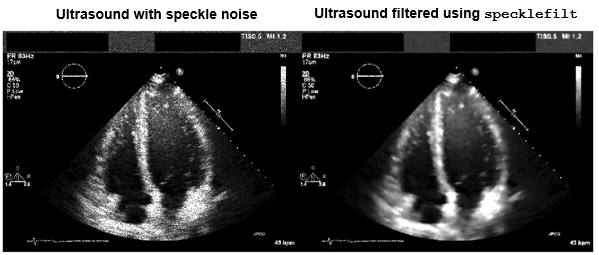

Denoising

Medical imaging modalities are susceptible to noise, which introduces random intensity

fluctuations in an image. To reduce noise, you can filter images in the spatial and

frequency domains. Medical Imaging Toolbox™ provides the specklefilt

function, which reduces the speckle noise common in ultrasound images. For additional image

filtering tools, see Image Filtering in Image Processing Toolbox™. You can also denoise medical image data using deep learning. For details, see

Train and Apply Denoising Neural Networks.